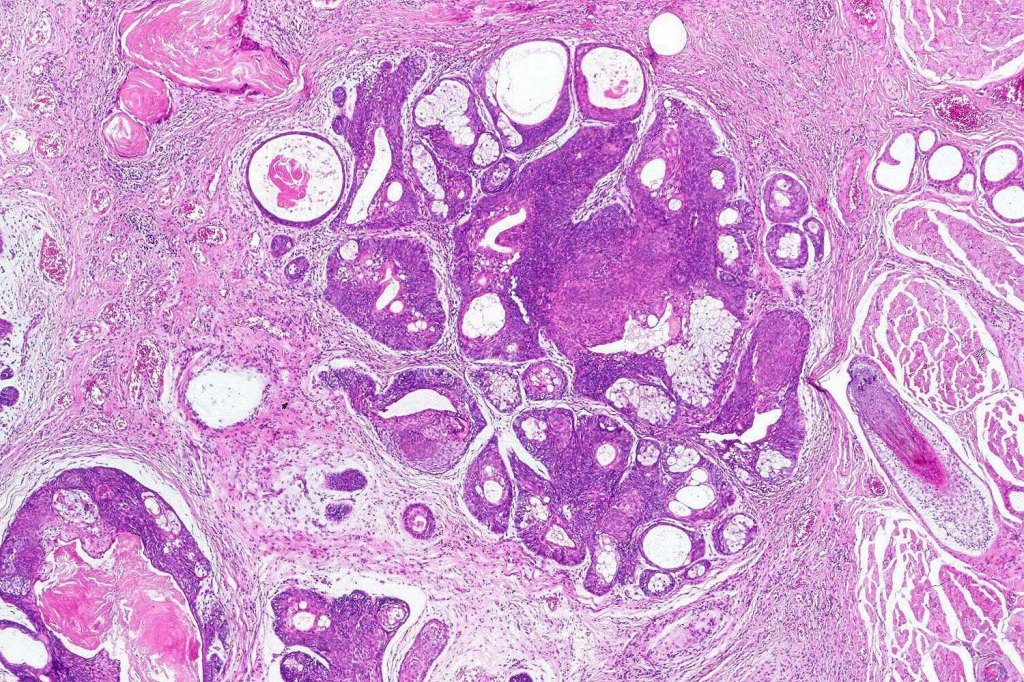

Histological features

•Variable origin from epidermis

•Typically multilobulated, occasioanlly cystic

•Collagenous pseudocapsule

•At the periphery, single or multiple germinative cell layers maturing into typical sebaceous cells (>50%)

•Variable peripheral palisading

•+/- basal mitoses (particularly in the so-called giant variant which should not be misdiagnosed as sebaceous carcinoma)